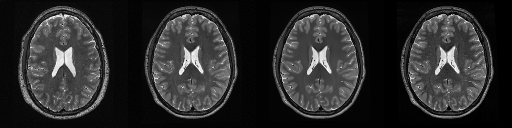

HCP T2w dataset

We utilize images from the publicly available Human Connectome Project (HCP) [51] T2-weighted (T2w) images dataset for the task of compressed sensing, which contains brain images from 47 patients. The HCP dataset includes cross-sectional images of the brain taken at different levels and angles.

Compressed sensing

We train a flow-based model from scratch on 10,000 randomly sampled images, utilizing the ncsnpp architecture [9] with minor adaptations for grayscale images. We employ compression rates , meaning . The measurement operator is given by a subsampled Fourier matrix, whose sign patterns are randomly selected. We evaluate our reconstruction algorithm’s performance on 200 randomly sampled test images.

We present the quantitative and qualitative results of compressed sensing in Tab. 1 and Fig. 4, respectively. As shown in Tab. 1, our method consistently achieves the best performance across varying compression rates . In Fig. 4, our method produces reconstructions that are more faithful to the original images, with fewer artifacts, leading to higher accuracy and clearer details.